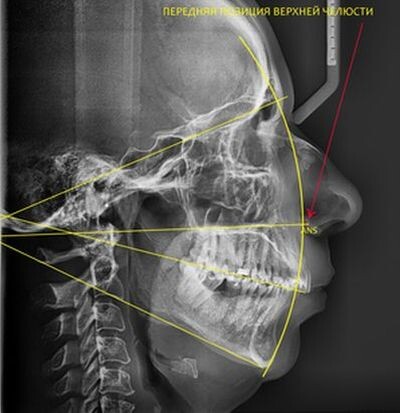

Передняя позиция (антепозиция) верхней челюсти.

А если верхняя челюсть нормального размера, но смещена кпереди? Здесь я бы показал бы пациента остеопату. И посмотрел бы на его череп и позвоночник. Позиция челюстей "железобетонно" завязана с позицией шейных позвонков. И коррекция проблем позвоночника (в частности его шейного отдела) может помочь "вернуть" верхнюю челюсть на место. А стало быть поможет избавит пациента от удаления зубов.